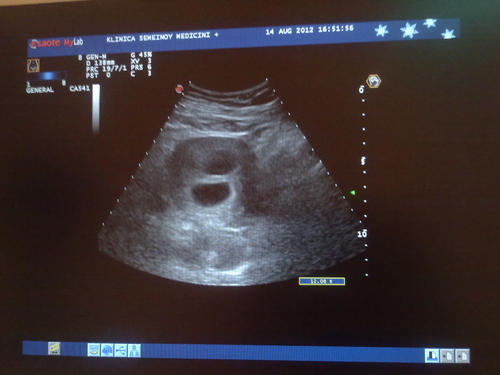

УЗИ двухплодной беременности на 5 неделе: Подборка изображений

Раздел: Калейдоскоп образов